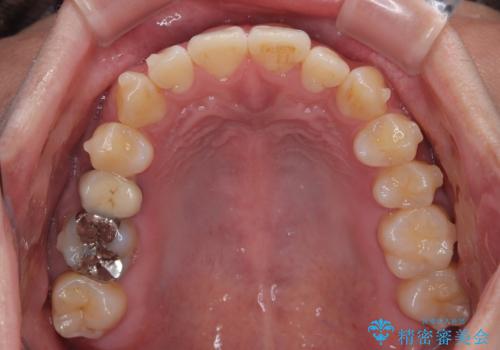

- 前歯の反対咬合などを気にして来院された患者様です。

ワイヤー矯正、マウスピース矯正どちらでも対応可能であったので、ご本人の希望によりインビザラインにて矯正治療を行うこととしました。

毎日の装着時間をしっかりと守ってくださり、1年強の短期間で、あっという間に治療を終えることができました。